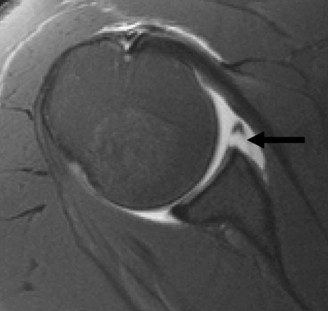

Advanced Cross Sectional Imaging

Given the radiographic evidence of bipolar bone loss (bony Bankart and Hill-Sachs lesion) in a high-demand collision athlete, a non-contrast computed tomography scan with three-dimensional reconstructions was mandated to precisely quantify the osseous defects.

The CT scan utilizing the Pico surface area method, which involves a best-fit circle drawn on the inferior portion of the glenoid on the en face sagittal view, revealed a 22% anterior glenoid bone loss. The fragment was comminuted and non-reconstructable. Furthermore, axial and coronal reconstructions were utilized to evaluate the Hill-Sachs lesion. The impaction fracture was measured for depth, width, and length.

To fully assess the soft tissue envelope, a Magnetic Resonance Arthrogram was subsequently performed. The MRA confirmed a complete avulsion of the anteroinferior capsulolabral complex extending from the 3 o'clock to the 6 o'clock position. The inferior glenohumeral ligament was stripped from the glenoid neck, consistent with an anterior labroligamentous periosteal sleeve avulsion variant. The rotator cuff tendons were contiguous and demonstrated no full-thickness or high-grade partial-thickness tearing. The long head of the biceps tendon was centered within the bicipital groove without evidence of superior labrum anterior and posterior pathology.